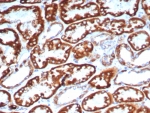

IHC staining of FFPE human kidney tissue with FGF23/6406 at 2ug/ml. HIER: boil tissue sections in pH 9 10mM Tris with 1mM EDTA for 20 min and allow to cool before testing.